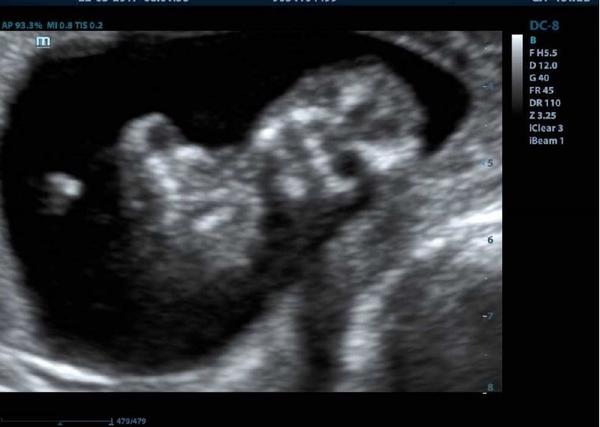

@tercasv ony ty cizí fotky na internetu jsou něco jiného, než když pak člověk vidí toho svého cvrčka 🙂 Mě tedy zase tak moc neoslovily přímo ty fotky - byť se nám povedly docela hezky, ale líbil se mi ten zážitek. Je vidět, jak se tam miminko tváří, jak zívá, dělá ksichtíky........🙂

@michaela_2 Zážitek to musí být určitě krásny 🙂 Na klasickém utz (vaginálním) jsem úplně na měkko, když vidím srdíčko, ale ty 3D fotky mě neohromily :D Ale říkám si, že je to naše první miminko, tak by bylo hezký mít ty fotky v albu 🙂

Musím říct, že to bylo super. Přesto, že nejsem zrovna hubená a mám placentu na přední straně, tak bylo mimčo krásně vidět. Oproti těm skoro mazaninám od gynekologa nesrovnatelné....

Takže doporučuju. Myslím si, že to tatínkovi pomůže vytvořit si i nějaký vztah k mimču. Když ho takhle uvidí na videu, jak se tam hýbe, zívá, strká si pěstičku do pusinky atd. 🙂